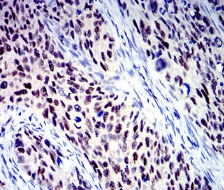

IHC    1/200 - 1/1000